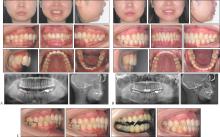

隐形矫治技术发展20多年,已从单纯的牙齿排齐工具发展为多学科口腔治疗的核心手段,尤其在牙周病正畸治疗、颞下颌关节紊乱病(TMD)正畸治疗、修复种植正畸联合治疗及正畸正颌联合治疗中展现显著优势。牙周病正畸治疗的目标是促进健康与稳定。建议牙周炎症控制后介入正畸治疗,实行轻力渐进原则,减少牙移动步距,减少隐形矫治器包裹,延长牙套替换时间。TMD正畸治疗的目标是咬合—关节协调,解除咬合创伤,稳定关节功能,排齐牙列,改善咬合。正畸介入时机仅适于稳定期TMD,强调多学科联合管理,患者正畸治疗的知情同意非常重要。修复种植正畸联合治疗的目标是空间与美学整合。隐形矫治的数字化设计可集中间隙,拓展修复种植空间,压低伸长对颌牙,直立倾斜的基牙,为修复种植提供理想的𬌗龈距离及近远中径,配合微笑设计等提升红白美学指数。严重骨性畸形的正畸正颌联合治疗可实现正畸—手术精准协同。隐形矫治数字化设计,上下牙弓宽度匹配相对固定矫治更容易实现,有效减少椅旁操作时间,提升矫治效率。目前隐形矫治在多学科领域里的应用还相对有限,高质量研究也不多,期待未来有更多高质量的研究以提高对隐形矫治的认识,让更多患者能精准高效地完成隐形矫治。

Clear aligner treatment has evolved over the last 20 years. It has transformed from a simple tool for tooth alignment to an essential component of multidisciplinary oral treatment. It has shown significant advantages in the orthodontic treatment of periodontal disease, the orthodontic treatment of temporomandibular joint disorder (TMD), integrated approaches with dental implant restoration, and the combined treatment of orthodontics and orthognathic surgery. The objective of orthodontic treatment for periodontal disease is to enhance health and stability. Commencement of clear aligner treatment is advised after the management of periodontal inflammation. The principle of applying gentle and gradual force must be adhered to. The extent of tooth movement should be reduced. The coverage of the aligner should be minimized. The time between aligner replacements should be extended. The objective of orthodontic treatment for TMD is to achieve occlusal-joint coordination, eliminate occlusal trauma, stabilize joint function, align the teeth, and improve occlusion. Clear aligner intervention is only suitable for stable TMD. Emphasis is placed on collaborative multidisciplinary management. Informed consent for orthodontic treatment of patients with TMD is crucial. The goal of combined orthodontic and restorative treatment is to integrate space and aesthetics. The digital design of clear aligners can optimize spacing, expand the area for dental implants, intrude over-erupted opposing teeth, upright tilted abutment teeth, ensure optimal gingival distance and mesiodistal diameter for dental implants, and when combined with smile design, it can significantly improve the pink and white aesthetic score. Precise orthodontic-surgical coordination is achieved for the combined treatment of severe skeletal malocclusion via orthodontics and orthognathic surgery. The digital design of clear aligners facilitates the alignment of the upper and lower dental arches more effectively compared with fixed orthodontic treatment. It effectively reduces chairside operation time and significantly improves treatment efficiency. At present, the application of clear aligners in multidisciplinary fields remains limited, and high-quality studies are lacking. We anticipate further high-quality research in the future to enhance our understanding of clear aligner treatment. This will facilitate the exact and rapid completion of clear aligner therapy for patients, resulting in aesthetically pleasing smiles.